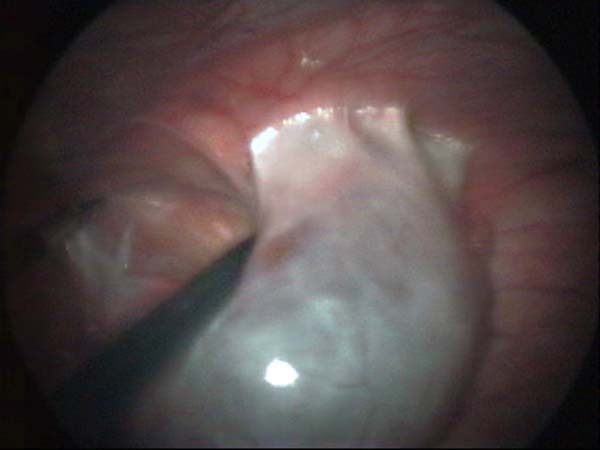

Laparoscopy Photos Ovarian Cyst Ovarian Cystectomy Uterine Septum Tubal Pregnancy